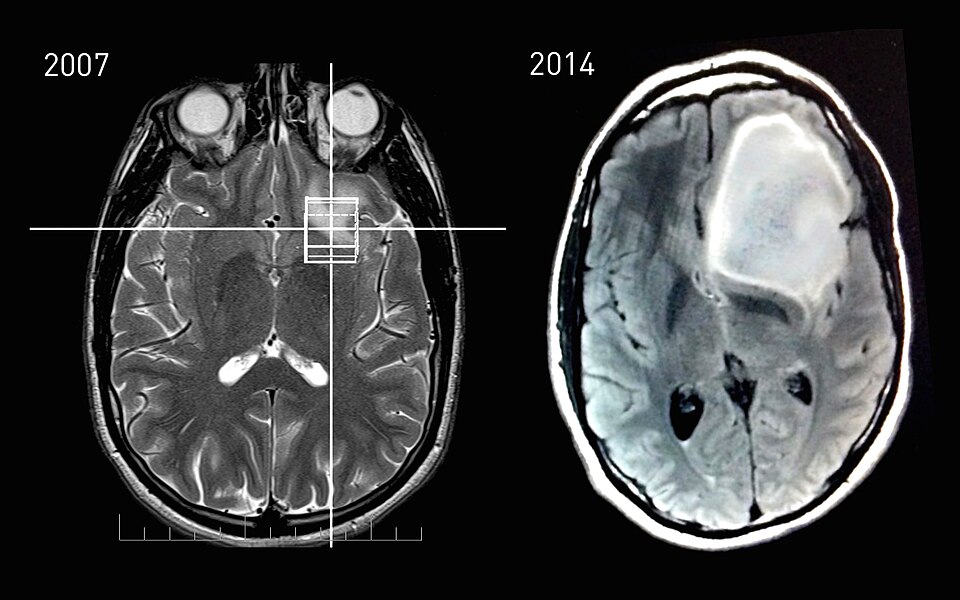

Untuk mendiagnosis astrositoma, dokter biasanya melakukan pemeriksaan neurologis terlebih dahulu. Jika ditemukan indikasi adanya gangguan, pasien akan menjalani pemeriksaan pencitraan seperti MRI (Magnetic Resonance Imaging) atau CT scan untuk melihat adanya massa di otak.

Prognosis pasien Astrositoma sangat bervariasi. Pada tumor derajat rendah yang dapat di angkat sepenuhnya, peluang hidup jangka panjang cukup baik. Namun, pada tumor agresif seperti glioblastoma, tantangan pengobatan lebih besar.